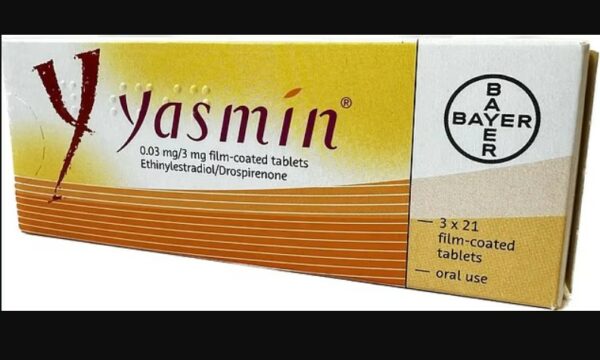

Kontraceptivi i përdorur nga miliona gra shkakton vdekjen e një 29-vjeçareje të shëndetshme

Alarmon studimi i ri: Pilula kontraceptive e përdorur nga miliona gra mund të trefishojë rrezikun e sulmeve në tru

Kontraceptivi i përdorur nga miliona gra shkakton vdekjen e një 29-vjeçareje të shëndetshme

Alarmon studimi i ri: Pilula kontraceptive e përdorur nga miliona gra mund të trefishojë rrezikun e sulmeve në tru

Doktorët paralajmërojnë një grup grash për pilulat kontraceptive